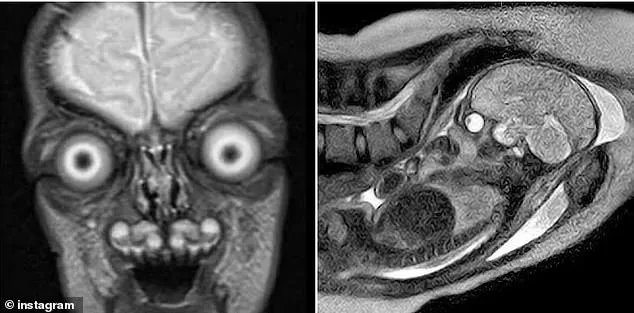

Disturbing images of fetal MRI scans have sparked renewed public debate about the safety of performing magnetic resonance imaging on pregnant women. These images, which reveal the skeleton of an unborn baby in stark white against darker soft tissue, have circulated online, prompting concern and curiosity among expectant mothers and the general public. The clarity of the scans, which can show individual finger bones, the full spine, and even the skull, has left some viewers unsettled, questioning the potential risks of the procedure.

MRIs are reserved for specific situations, such as diagnosing tumors, spinal cord injuries, or brain structural abnormalities. They can also reveal joint disorders or cartilage damage that might not be visible in an ultrasound. Despite their diagnostic value, MRIs can be uncomfortable for pregnant women, especially in the third trimester. The need to lie flat for extended periods can compress major blood vessels, and the confined space of the MRI machine may trigger claustrophobia or anxiety.

For parents facing a prescribed MRI, the scans often follow an ultrasound that raised concerns about the baby's health. While the detailed images can be anxiety-inducing, they also provide critical information that may help parents prepare for potential challenges. Despite the discomfort and psychological impact, the procedure remains a vital tool for diagnosing serious fetal conditions and ensuring timely medical interventions.